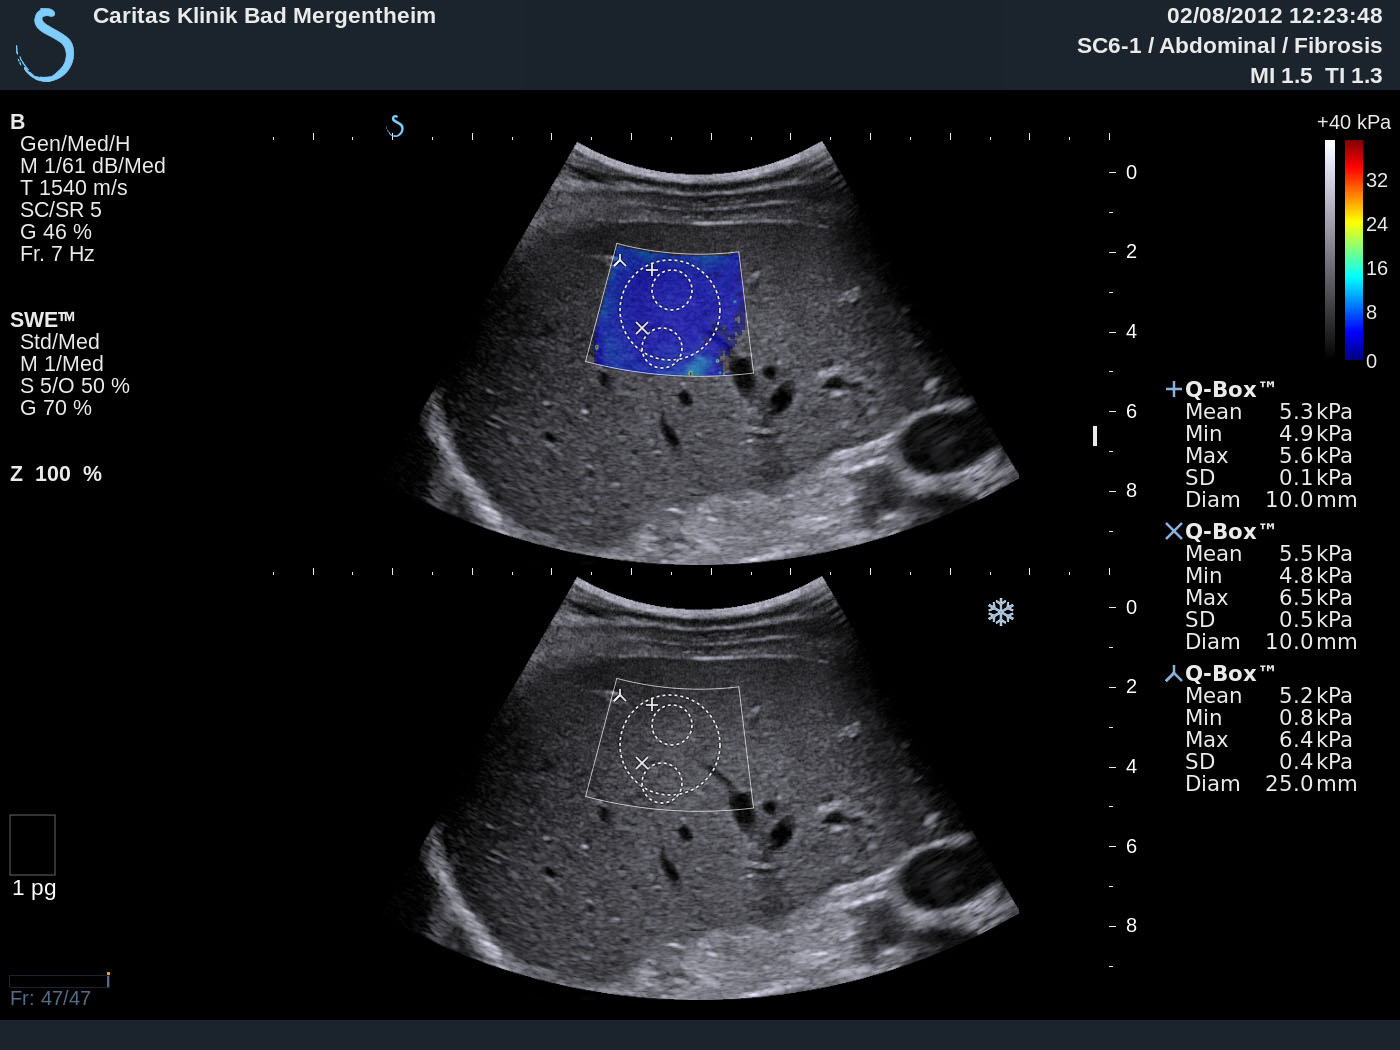

1 Case report We report on shear wave elastography using Supersonic Imaging (SSI) from a practical point. The procedure was repeated three times of three different scanning views in order to acquire three valid independent SWE™ maps. Examples are shown in Figure 1. The case reports in healthy subjects, patients with intermediate fibrosis and liver cirrhosis were summarized and analyzed to discuss basic principles, imaging acquisition, data reproducibility, advantages and limitations of this method as part of the Shear Wave Elastography Research Group activities (SWERG).

3.2.6 SWE™ stiffness quantification

Once the SWE™ map is satisfactory, freeze and select the Q-Box™ measurement tool. Resize its diameter to 15-20 mm if needed, place it preferably at the center of the SWE Box, over an area of relative homogeneous elasticity, at a depth of 3-5 cm; do not place it over an area with missing SWE™ pixels. On recent software versions of Aixplorer® liver package, a Stability Index has been added as an indicator of SWE map homogeneity and temporal stability. This index is displayed while positioning the built-in Q-Box™ quantification tool. A Stability Index below 90% should lead to the rejection of the Q Box™ location, and push the operator to find a better location. In the event no satisfactory location can be found on a given frozen SWE™ map, a new SWE™ acquisition should be performed.